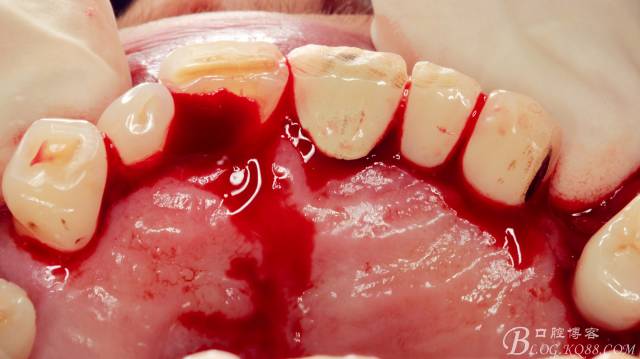

局麻下做齦溝內(nèi)切口

翻瓣,長柄球鉆清掃薄薄的骨皮質(zhì),暴露出牙冠,動作一定要輕柔,感覺就像在雞毛撣子一樣撣花瓶上的灰一樣,因為骨和牙釉質(zhì)有明顯的密度差異,手感上面差別比較明顯。